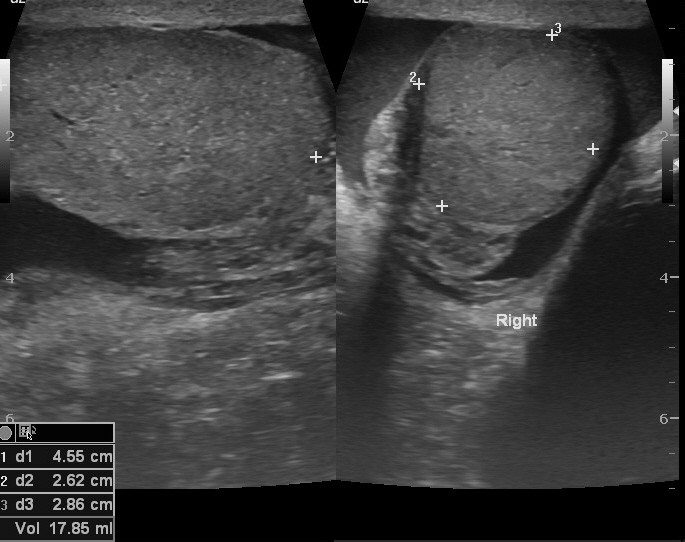

USG jąder pozwala na ocenę zawartości worka mosznowego: jąder, najądrzy, ich osłonek i obecności żylaków powrózka nasiennego. Powinno być wykonane w każdym przypadku bólu jąder, powiększenia moszny, wyczuwalnego guzka, wycieku z cewki moczowej. Przy braku jądra w worku mosznowym pozwala na ustalenie przyczyn tego stanu. Dodatkowym wskazaniem do wykonania USG jąder są niepowodzenia w rozrodzie. Nie wymaga żadnego przygotowania. Badanie wykonywane jest u pacjentów w każdym wieku, jest bezbolesne, może być powtarzane wielokrotnie bez narażania pacjenta na szkodliwe promieniowanie.